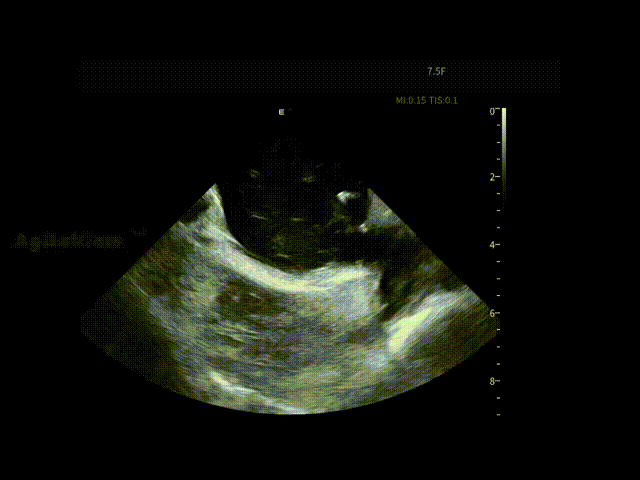

随后,术者选择在AgileView™ ICE的“PFA预设模式”下进行导管消融,在实时高清影像的指导下,PulseSelect™脉冲消融导管安全进入左心房,先后完成双侧肺静脉隔离及后壁消融,ICE PFA预设模式下可见画面成像清晰,导管贴靠良好,整个消融过程顺利高效,消融时间仅30分钟(PVI+PWI)。术后患者恢复良好。

在消融过程中,ICE提供的实时高清成像帮助术者动态观察消融导管与心房组织的空间关系与贴靠状态,使关键步骤判断更加可视、可靠。